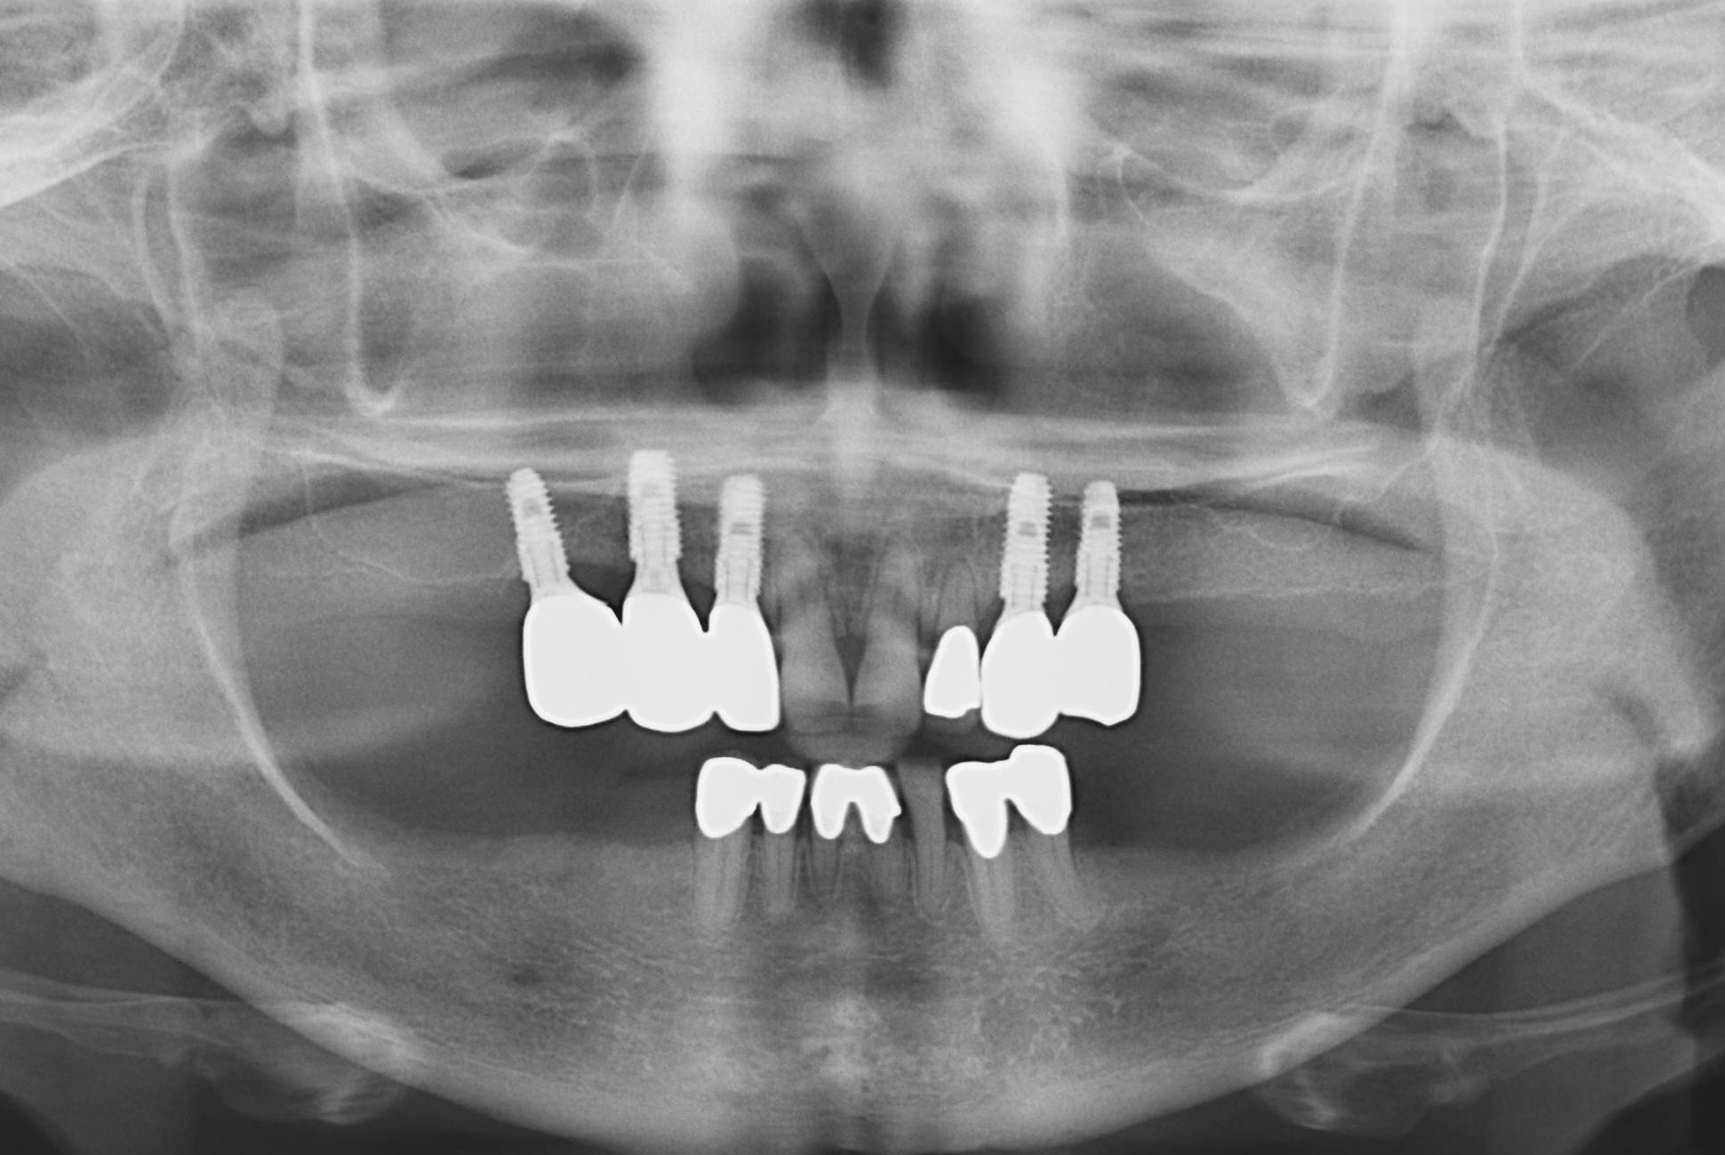

Objectives: Implant-assisted removable partial dentures (IARPDs) have been proposed as a treatment option for partial edentulous patients. However, evidence regarding the merits of implant-assisted removable partial dentures with implant surveyed prostheses is limited. This study was conducted to evaluate the clinical status and complications of IARPDs combined with implant surveyed prostheses in terms of clinical condition, marginal bone resorption, and prosthetic complications.

Methods: Patients treated by IARPDs combined with implant surveyed prostheses and had worn an IARPD at least 12 months were included. 24 patients (25 cases, 12 maxilla and 13 mandible) were selected, and 80 implants used as abutments for IARPDs were surveyed. Average follow-up was 27.6 months and maximum follow-up was 78 months. Implant cumulative survival rate, marginal bone resorption, probing depth, peri-implant inflammation, bleeding, plaque, calculus, and complications were evaluated.

Results: No implant failure was occurred and all implants functioned without clinical mobility. Mean marginal bone resorption of implants at 1 year after loading was 0.772 ± 0.63 mm, and mean probing depth was 3.36 ± 0.06 mm. No patient developed peri-implantitis and no implant failed. Two clasp fractures, one rest fracture, de-cementation, and a porcelain fracture of implant surveyed prostheses were detected at 12 months after loading.